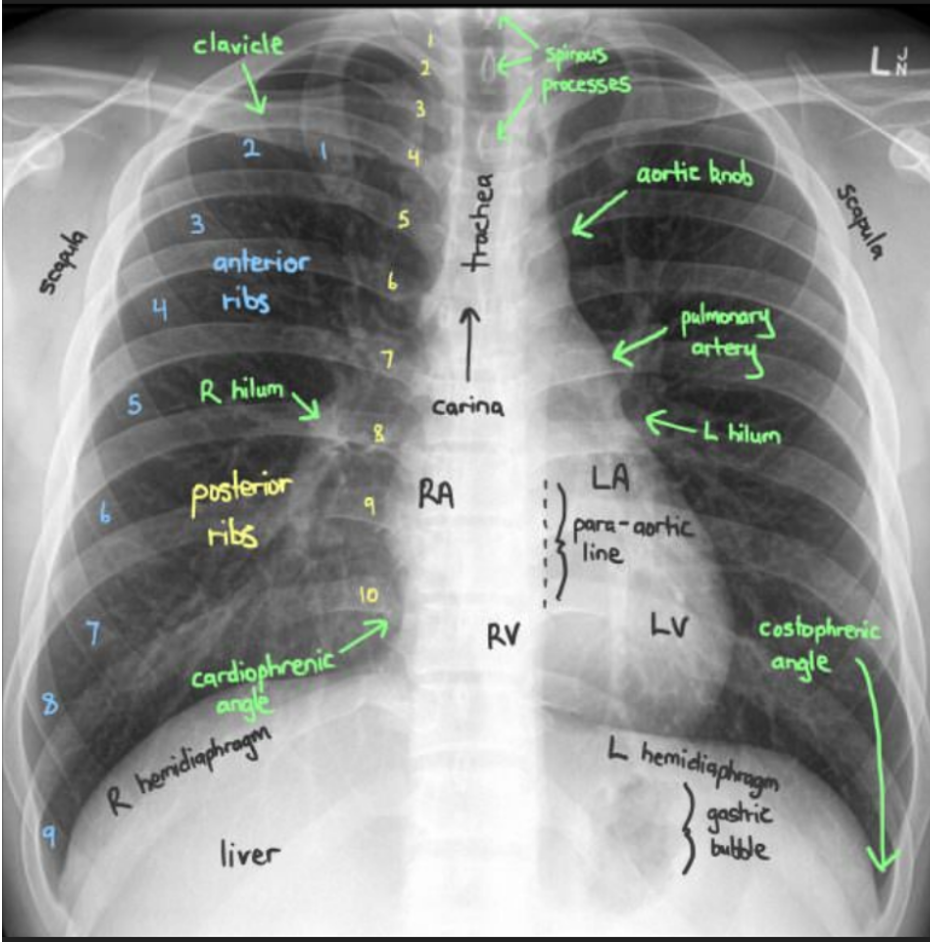

Airway

A

tracheal central?

breathing

• Lung fields (opacification)

• Upper

• Middle

• Lower

• Costophrenic angles

• Compare left lung to right lung

circulation

• Aortic knuckles

• L and right hilar region

• Heart size

• Cardiothoracic ratio

• Cardio phrenic angle

Diaphragm

compare both sides

• Tented?

• Flattened?

• Pneumoperitoneum?

• Gas in stomach normal